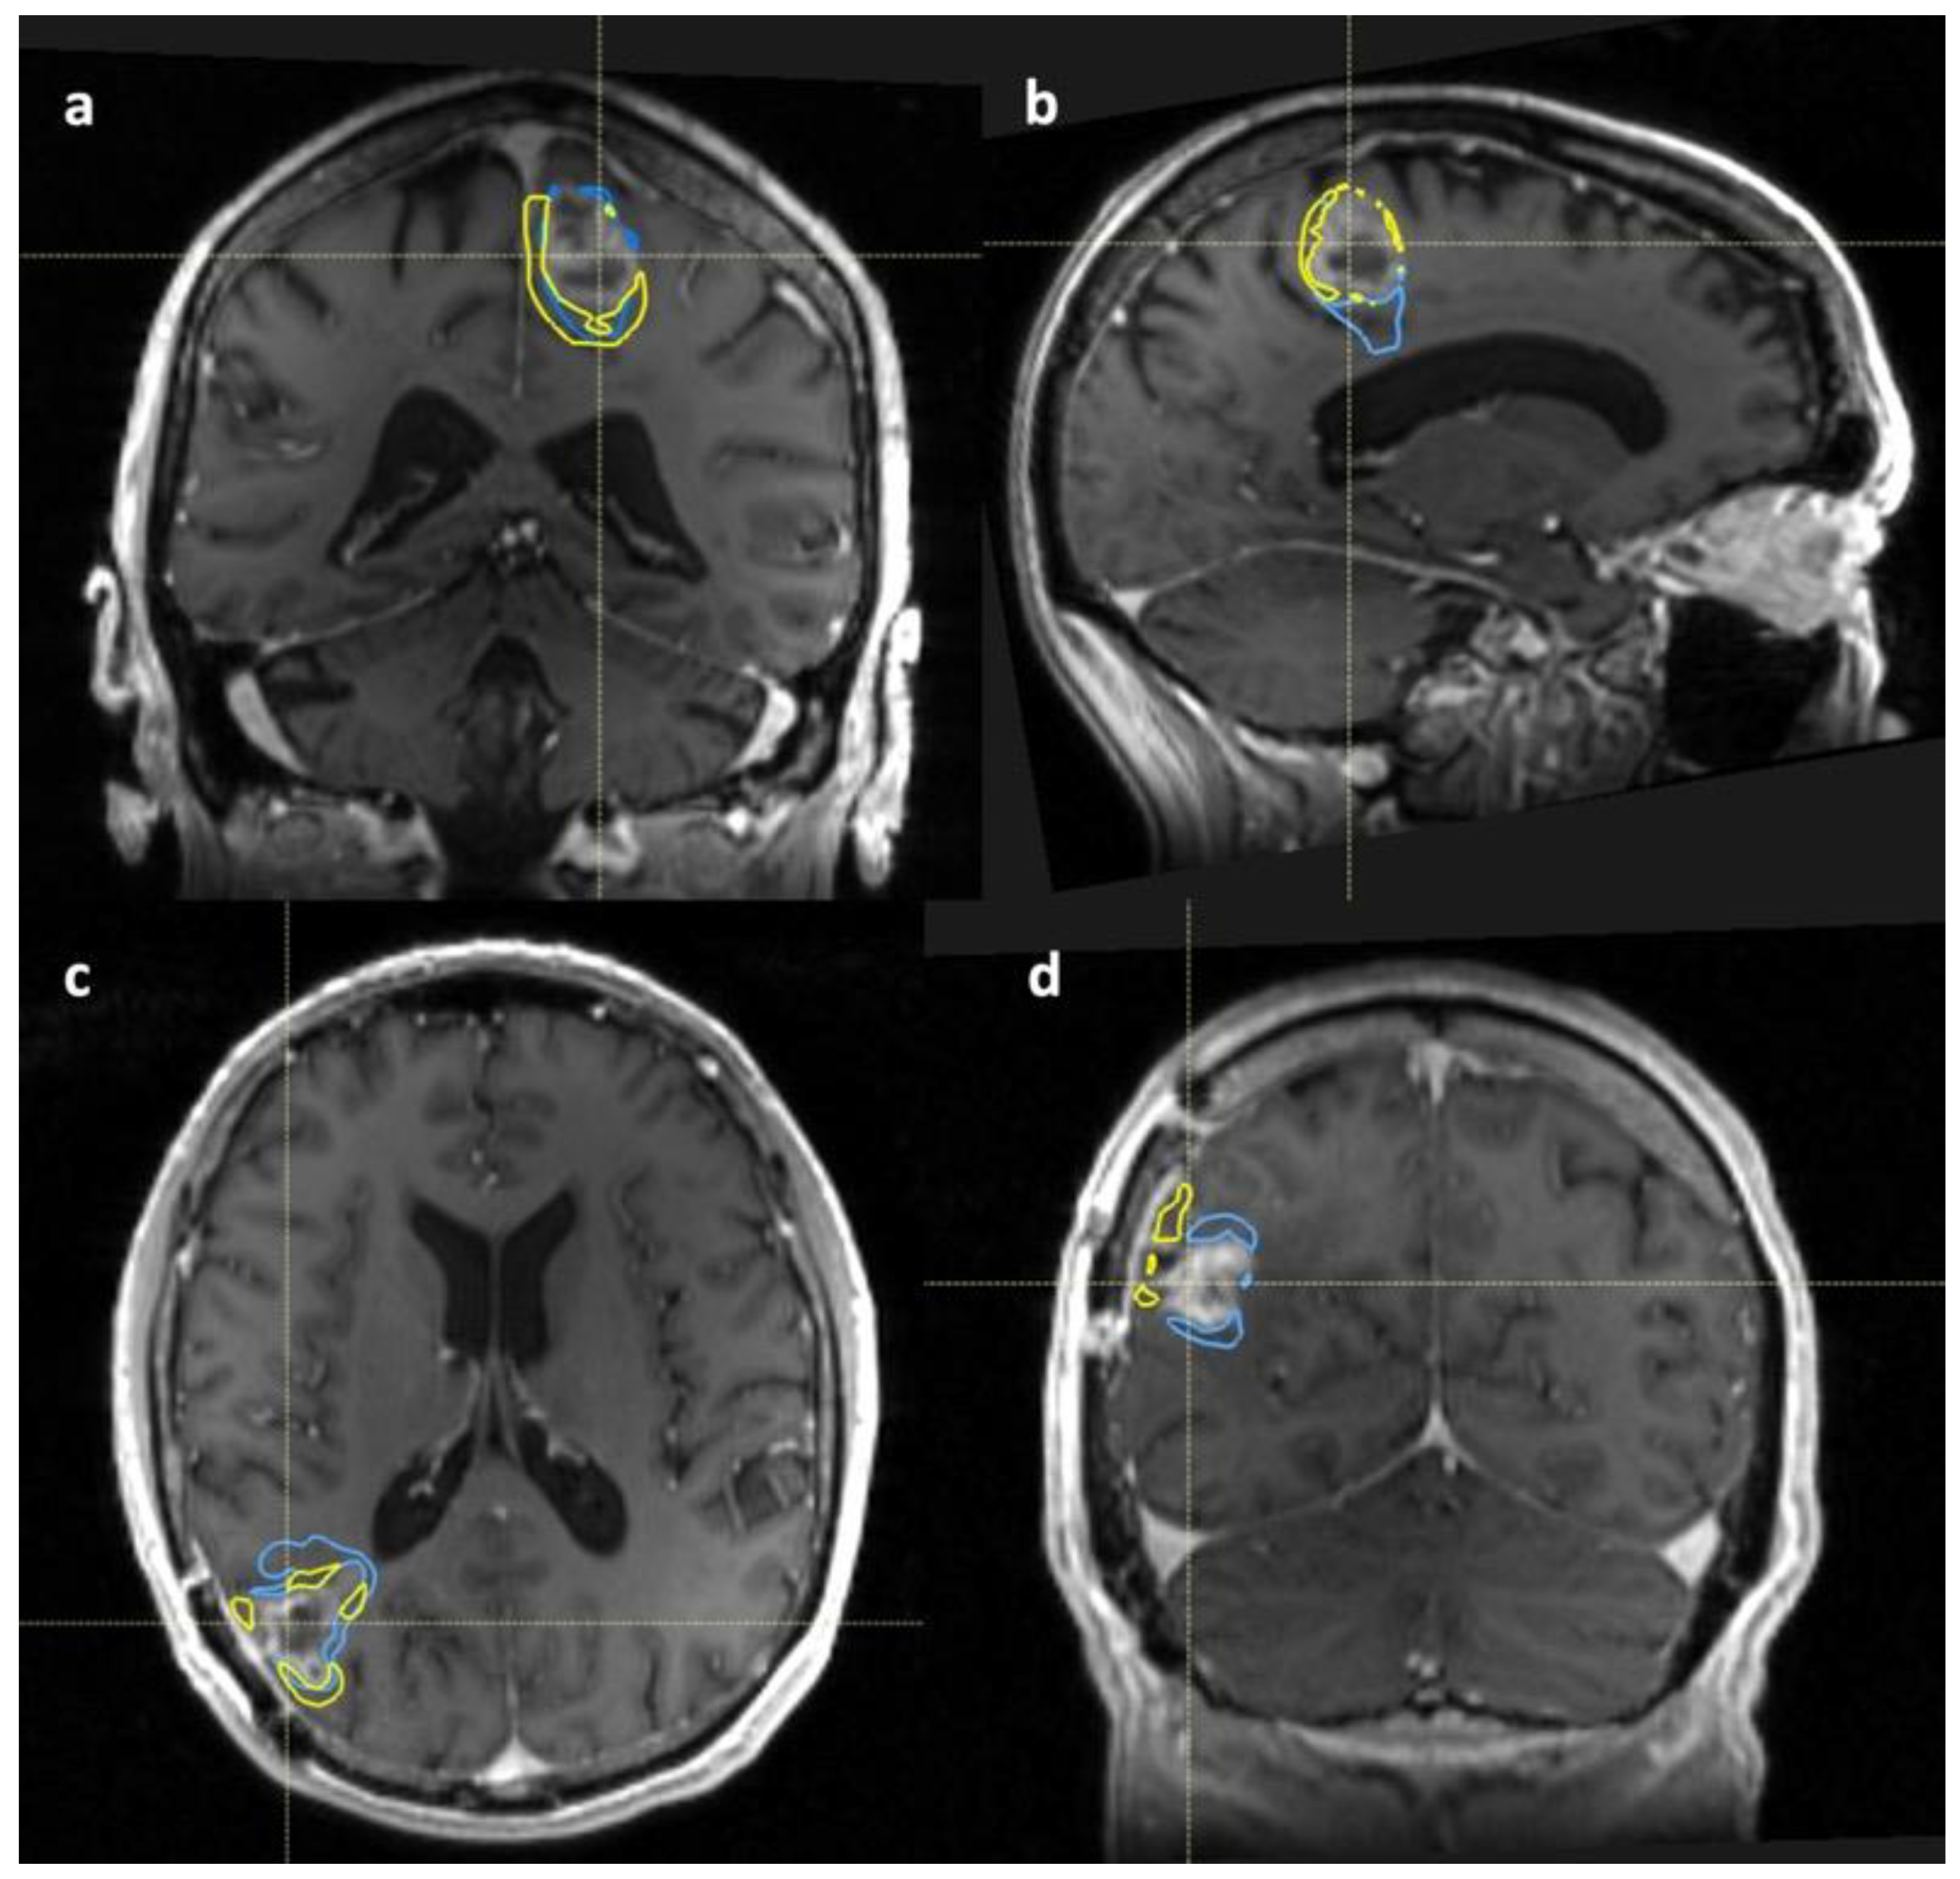

3.2.2. Tumour Volume Analysis

Subtracted Volumes

3.3. Pre-Clinical Results